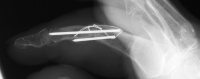

| PIP fusion with tension

band technique. |

| Late result. |